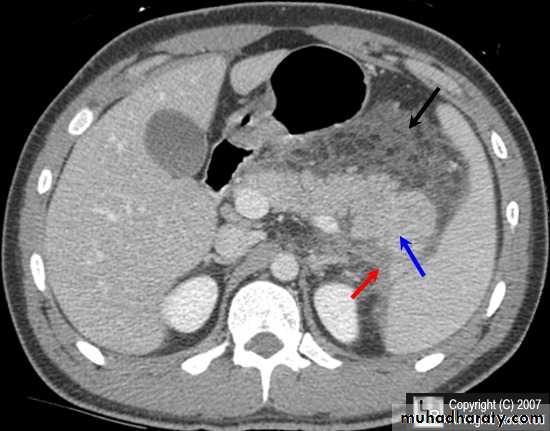

Acute Pancreatitis

CT used to

• 1. Pancreatic necrosis .• 2. An abscess.

• 3. Vascular complications.

• 4. Pseudocyst